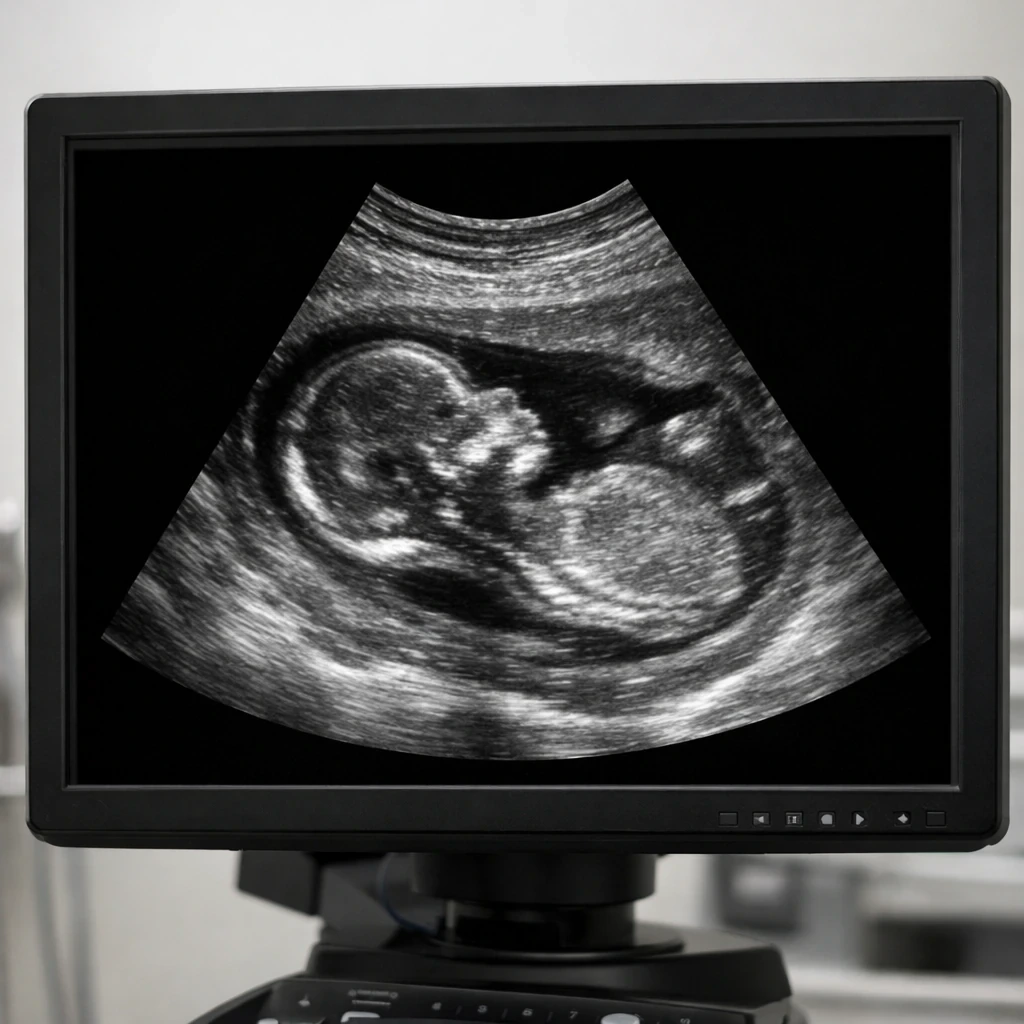

تکنولوژی های نوین در سونوگرافی رنگی طی سال های اخیر تحول بزرگی در حوزه تشخیص ناهنجاری های جنینی ایجاد کرده اند، امروزه دیگر سونوگرافی صرفاً یک تصویر ساده سیاه و سفید نیست بلکه به ابزاری دقیق پیشرفته و چند بعدی تبدیل شده است که می تواند ساختار های بسیار ظریف جنین را با وضوح بالا نمایش دهد، برای هر پدر و مادری مهم است که از سلامت جنین خود اطمینان داشته باشند و برای هر پزشک متخصص نیز مهم است که بتواند با بیشترین دقت ممکن ناهنجاری های احتمالی را در زمان مناسب تشخیص دهد، در این مقاله به صورت جامع و تخصصی بررسی می کنیم که تکنولوژی های جدید در سونوگرافی رنگی چگونه به افزایش دقت تشخیص کمک می کنند و چه عواملی باعث می شود نتیجه نهایی به حداکثر دقت برسد.

تکنولوژی سه بعدی و چهار بعدی تحول چشمگیری در ارزیابی ناهنجاری های ساختاری ایجاد کرده است، در تصویربرداری سه بعدی تصویر حجمی از اندام های جنین ساخته می شود و پزشک می تواند ساختارهایی مانند صورت ستون فقرات اندام ها و دیواره شکم را با دقت بیشتری بررسی کند، در تصویربرداری چهار بعدی حرکت در زمان واقعی نیز اضافه می شود و بررسی حرکات جنین و عملکرد اندام ها امکان پذیر می گردد.

این فناوری در تشخیص شکاف لب و کام ناهنجاری های اندام و برخی مشکلات اسکلتی بسیار مؤثر است، علاوه بر جنبه تشخیصی به والدین نیز کمک می کند درک بهتری از وضعیت جنین داشته باشند و ارتباط عاطفی قوی تری برقرار کنند، اما نکته مهم این است که استفاده از این فناوری باید توسط متخصص آموزش دیده انجام شود تا تفسیر تصاویر دقیق باشد.